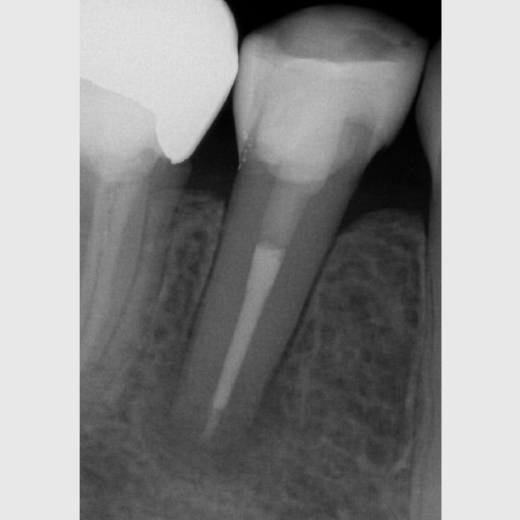

Fallbeispiel: Revision 46 (und 45) Recall 6 Monate

Bringt eine Wurzelkanalbehandlung nicht den gewünschten Erfolg, bedeutet dies nicht, dass ein Zahn nicht mehr zu erhalten ist. Mit einer Revisionsbehandlung können auch bereits wurzelkanalbehandelte Zähne langfristig erhalten werden!